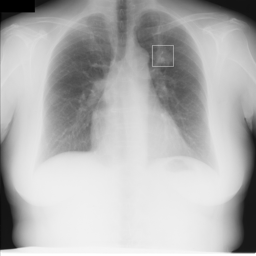

病変部位が四角で囲われています。